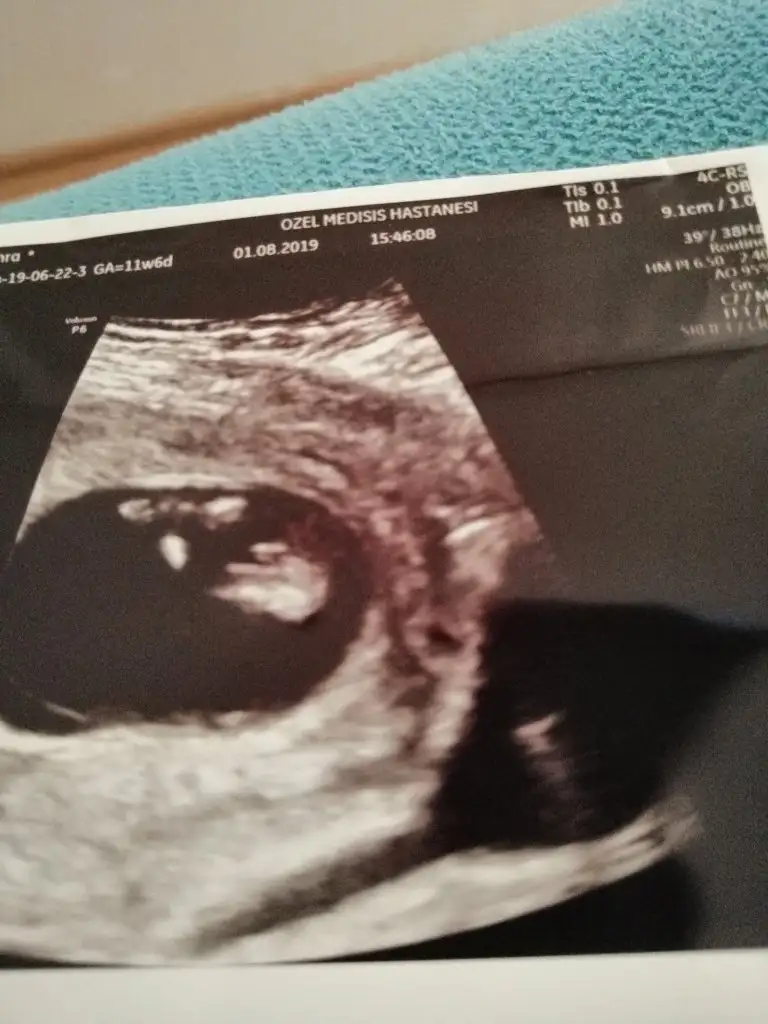

Erkek gibi11 haftalıktahmin alabilirmiyim

Erkek gibi kafa sekline yorumluyorum nub artık olmaz 13 hafta sanırımArkadaşlar daha önce yorum yapmıştınız ama doktor kesin bişey söylemiyor bunada bakabilir misiniz

Evet teşekkür ederimmmErkek gibi kafa sekline yorumluyorum nub artık olmaz 13 hafta sanırım